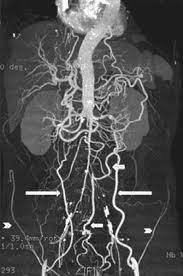

leriche syndrome (aorto-occlusive disease)

leriche syndrome